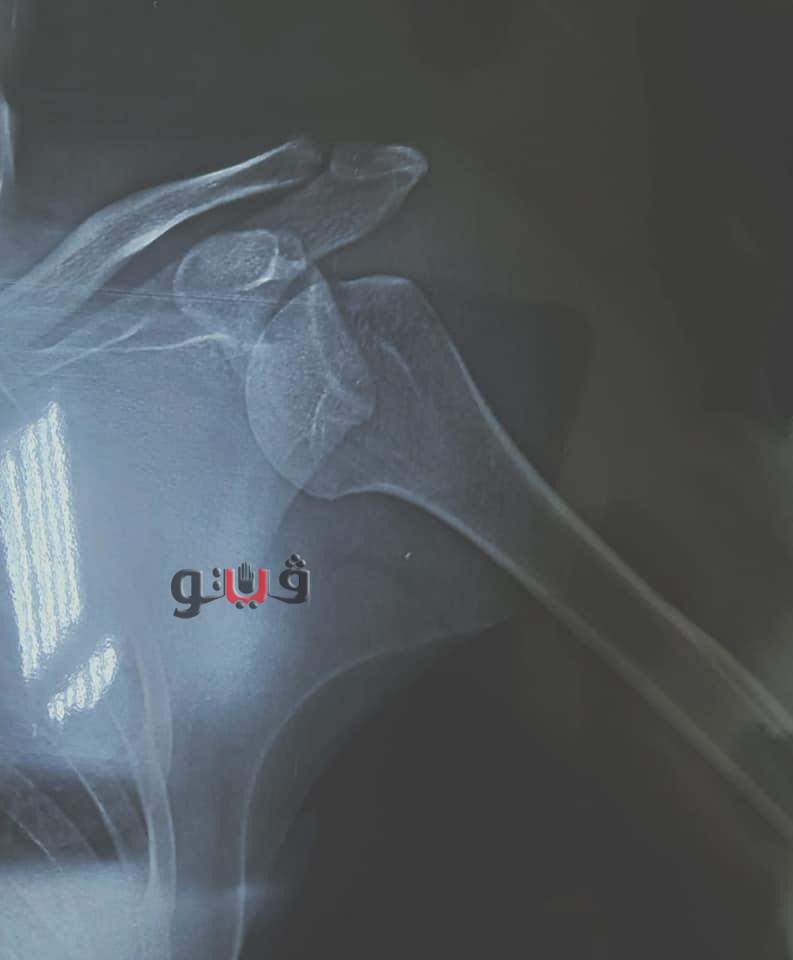

تعرض عمرو مصطفى مهاجم بلدية المحلة للإصابة

بخلع في الكتف وذلك في مران الفريق الأخير قبل مباراة كفر الشيخ والمقرر لها

وقام الجهاز الطبي لنادي بلدية المحلة بإجراء أشعة مقطعية على كتف اللاعب اثبتت إصابته بخلع في الكتف مما يستوجب الراحة لمدة شهر.

وأجرى الدكتور رؤوف فودة طبيب نادي بلدية المحلة عملية جراحية للاعب مساء الأمس وذلك لتثبيت كتف اللاعب على أن يقوم اللاعب بالعودة للتدريبات بعد شهر من موعد العملية الجراحية.